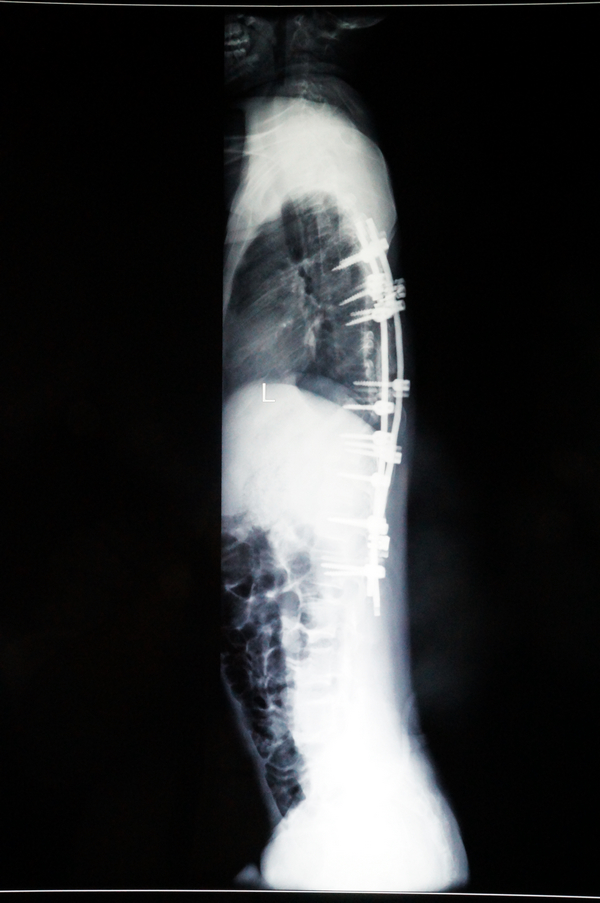

小松的爸妈懵了,他们央求医生一定要想办法帮小松把歪了的背给“扳直”。骨脊柱二区刘汝专主任和鲁世金主任等专家迅速组织了术前科室讨论,一致认为:小松的脊柱侧弯明显,脊柱侧凸严重影响了他的生长发育、外观,同时若放任侧凸发展下去,必然会压迫心脏、肺脏等器官,影响心肺功能,脊柱不平衡还会导致肌肉神经受牵拉,保守治疗无效,同时手术指征明确,宜马上施行手术。结合小松的临床症状和辅助检查,此次手术的目的在于纠正他的脊柱侧弯,恢复脊柱的稳定性,手术方式选择后路脊柱侧凸畸形矫形、椎弓根螺钉内固定植骨、肋骨截骨术。刘汝专主任等专家拟好了周详手术方案,还特别列出了术前术中的注意事项:术前注意测量设计好内固定物放置方式,并预计矫正角度;术中注意熟悉解剖,适当矫形,避免过度纠正,导致脊髓神经牵拉性损伤,固定要牢固;术后给予脱水、营养神经、预防感染等药物治疗。

现在,经过手术后的小松脊柱外观基本恢复了正常,他感到背部没有明显的疼痛,且背部的手术伤口也愈合良好,没有发热头晕头痛和恶心呕吐等不适症状,饮食睡眠都很好,四肢感觉、运动、肌力正常。

小松术后的X光片2